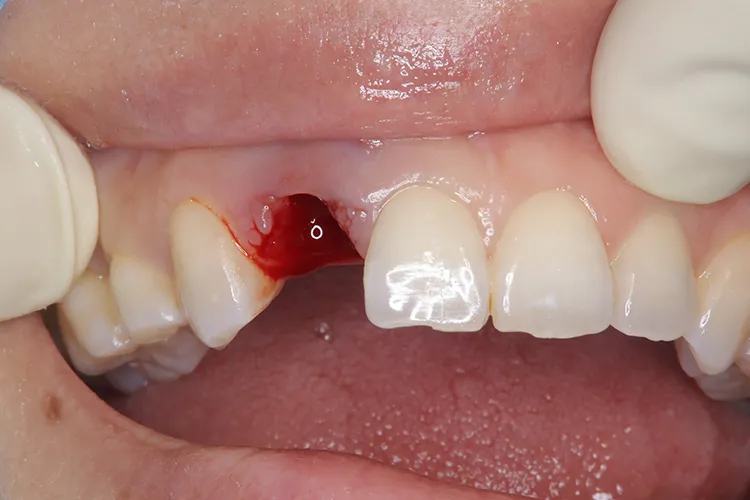

怪我で歯が折れてしまったケースです。前歯なので抜歯即時埋入で対応しました。即時で仮歯まで入れ、見た目の回復を行いました。その後歯肉が治りインプラントが安定したタイミングで最終の被せ物を装着しオペから3ヶ月で治療完了しました。